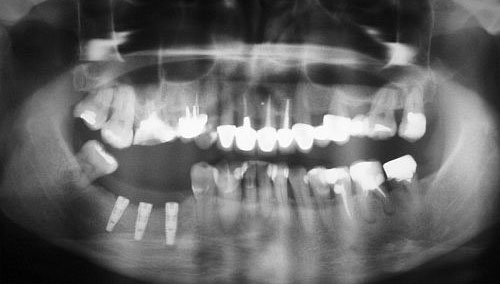

Zdjęcie pantomograficzne /panoramiczne/ – to podstawowe badanie radiologiczne, na podstawie którego możemy ocenić warunki kostne do wprowadzenia implantów dentystycznych.

Podstawowym, najistotniejszym czynnikiem dla powodzenia leczenia implantologicznego jest wystarczająca ilość kości, pozwalająca na wprowadzenie do niej wszczepów o odpowiedniej średnicy i długości. Jej ilość i jakość rzutuje na długoczasowość leczenia i właściwe efekty protetyczne i kosmetyczne. Badania radiologiczne wykonane przed zabiegiem pozwalają nam na dokładną ocenę warunków kostnych i położenia struktur anatomicznych w obrębie szczęk.

Wykonane w odpowiednie skali /np.1:1 lub 1:1,3/ pozwala nam na wykonanie dokładnych pomiarów interesujących nas struktur. Często, przed wykonaniem zdjęcia pantomograficznego do celów implantacyjnych umieszczamy w jamie ustnej tzw. markery, czyli metalowe kulki o średnicy 5 mm, które w obrazie rentgenowskim nie ulegają zniekształceniu. Dzięki nim, stosując później odpowiedni przelicznik związany ze skalą wykonanego zdjęcia mamy możliwość wykonania bardzo precyzyjnych obliczeń.

zdjęcie pantomograficzne

Na podstawie zdjęcia pantomograficznego możemy ocenić:

• stan kości (gęstość, obecność zmian chorobowych, stopień jej zaniku)

• wysokość wyrostka zębodołowego w miejscu planowanej implantacji

• stan zębów

• grubość błony śluzowej

• położenie i rozmiary zatok szczękowych

• przebieg nerwu zębodołowego dolnego

• położenie otworów bródkowych

• odległość do dna jamy nosowej